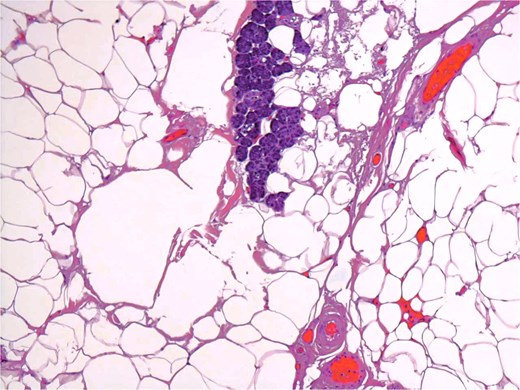

A 54-year-old male presented for assessment of a non-tender swelling in the left parotid region. His past medical history was unremarkable. Neck magnetic resonance imaging (MRI) revealed a well-defined adipose lesion in the left parotid gland measuring nearly 4.6 cm in its largest dimension. Neck ultrasound (US) additionally revealed bilateral thyroid nodules; Fine-needle aspiration of the right thyroid nodule confirmed benign follicular changes (Bethesda class II). Follow-up imaging (MRI and US) 1 year later showed a stable parotid lesion measuring 5.3 × 3.2 × 2.8 cm without contrast uptake. Bilateral thyroid nodules were unchanged. The patient was asymptomatic but reported cosmetic worries. Repeat imaging MRI demonstrated mild progression to 4.8 cm, expanding toward the parapharyngeal space. The lesion displayed uniform fat signal with no malignant enhancement. In view of gradual enlargement and patient cosmetic concern, surgical excision was recommended. A complete left parotidectomy with full general anesthesia was performed. During surgery, a lobulated, soft tumor measuring 6 × 4.5 × 2 cm was excised, while sparing all facial nerve branches. No complications were noted. Microscopic examination revealed a lobulated fibro-fatty tumor consisting of well-differentiated adipose tissue with intermixed salivary gland acini and ducts (Figs 1 and 2), establishing the diagnosis of sialolipoma. Postoperative recovery occurred without complications, and the patient showed normal facial nerve function at follow-up.

Small groups of acini, randomly distributed in lipomatous tumor.